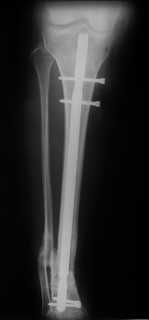

Произвели удаление проксимальной части штифта, далее рассверлили канал до 12 мм,Подвели и одели на конец отломка устройство с определенными техническими трудностями( проводник пришлось изогнуть, упиралось при входе в заднюю стенку, что значительно усложнило его последующее вращение, несколько раз удаляли устройство, т.к. полностью утрамбовывалось костной стружкой ) совместили отверстие на втулке и штифте и заблокировали отломком винта ( винт заранее надпилили по диаметру втулки и обломали после введения). Отломок удалился без проблем.Заштифтовали 11 мм реконструктивным штифтом, увы, устранить деформацию полность даже поллер винтами нам не удалось. Интраоперационно на экране ЭОпа оан выглядела не так критически, как на контрольных снимках после операции. Задним умом надо было отложить штифтование после репозиции в аппарате (прав был А.Н.Челноков!), слишком были заняты идеей удаления отломка штифта не оценив проблему устранения деформации. В п/операционном периоде разрешили дозированную нагрузку на конечность.С надеждой на критику и обсуждениеС уважением к сообществу В. Машталов

Судя по р/снимкам у Вас всё отлично получилось, то что немножко допустимое смешение осталось это видимо помешало сросшийся малоберцовка.